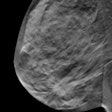

Studies show DBT detects more breast cancers than mammo